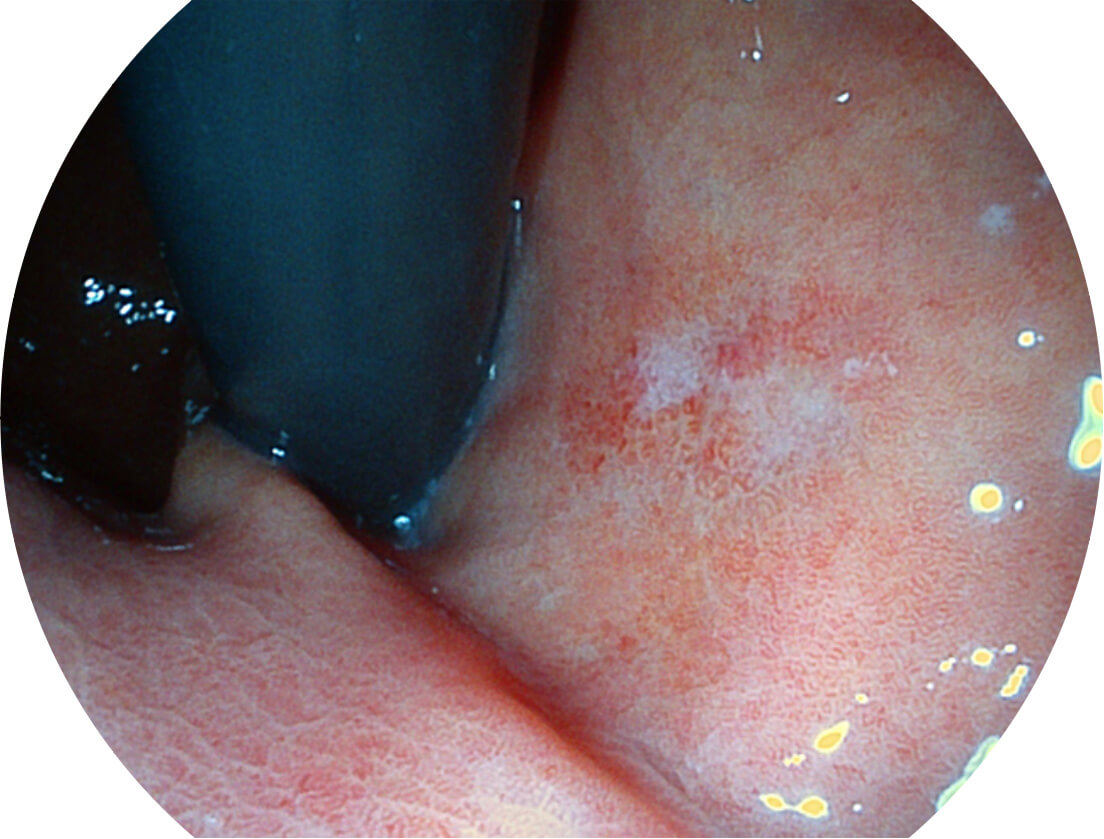

采用光路合束技术,光谱自由度高,实现了更丰富的照明模式,染色模式SFI及VIST,从远景到近景,助力消化道早期疾病诊断。

图像具有高亮度、高黏膜血管颜色对比度的特点,且不改变粘液、食物残渣、粪便的基本颜色,可在中远景下进行观察,助力消化道早期疾病的诊断。

强调浅层黏膜结构的同时,保证照明亮度和提升浅层微血管与中层血管颜色对比度,病变边界更清晰。